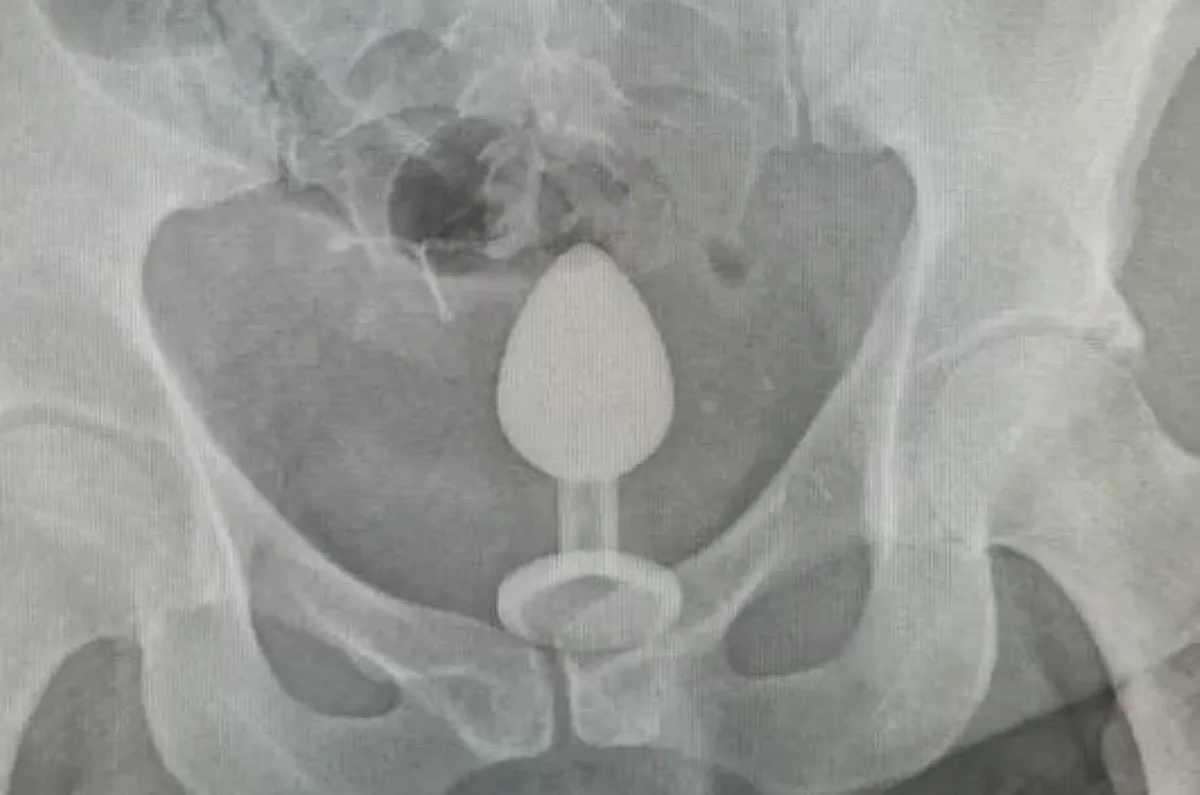

Ennek érdekében a férfi análkúpot dugott a felesége végbélnyílásába, majd megkezdték az aktust.

Ám az ütemes mozgások hatására a segédeszköz egyre mélyebbre vándorolt a nő fenekében, így azonnal megálltak.

Mivel eléggé felcsúszott a dugó, így a nő maga próbálta meg leszedni, azonban 40 percnyi forró fürdő sem segített rajta.

Így égő arccal, szégyenkezve ment be párjával a legközelebbi kórházba, ahol egy röntgenfelvétellel megállapították az eszköz helyzetét.

Az orvosok először műtéti úton akarták eltávolítani a pajzán játékszert, ám végül egy bevállalós rezidens szabadította meg Gigit az eszköztől.

Gumikesztyű és egy nagy adag vazelin segítségével sikerült kiszednie, rendkívül nagy fájdalmak árán.

Úgy sikoltoztam és ordítottam, mintha szülnék

– emlékezett vissza Gigi, akinek még epidurális érzéstelenítést is adtak.